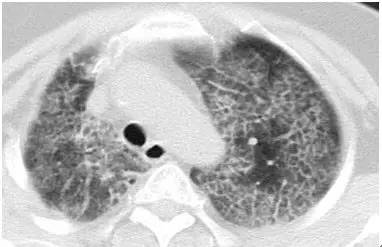

临床上,许多患者,现在会遇到同时发现肺内多发 GGO 病变。

4 个肿瘤一次全切除后,分别为 4 种类型的肺癌